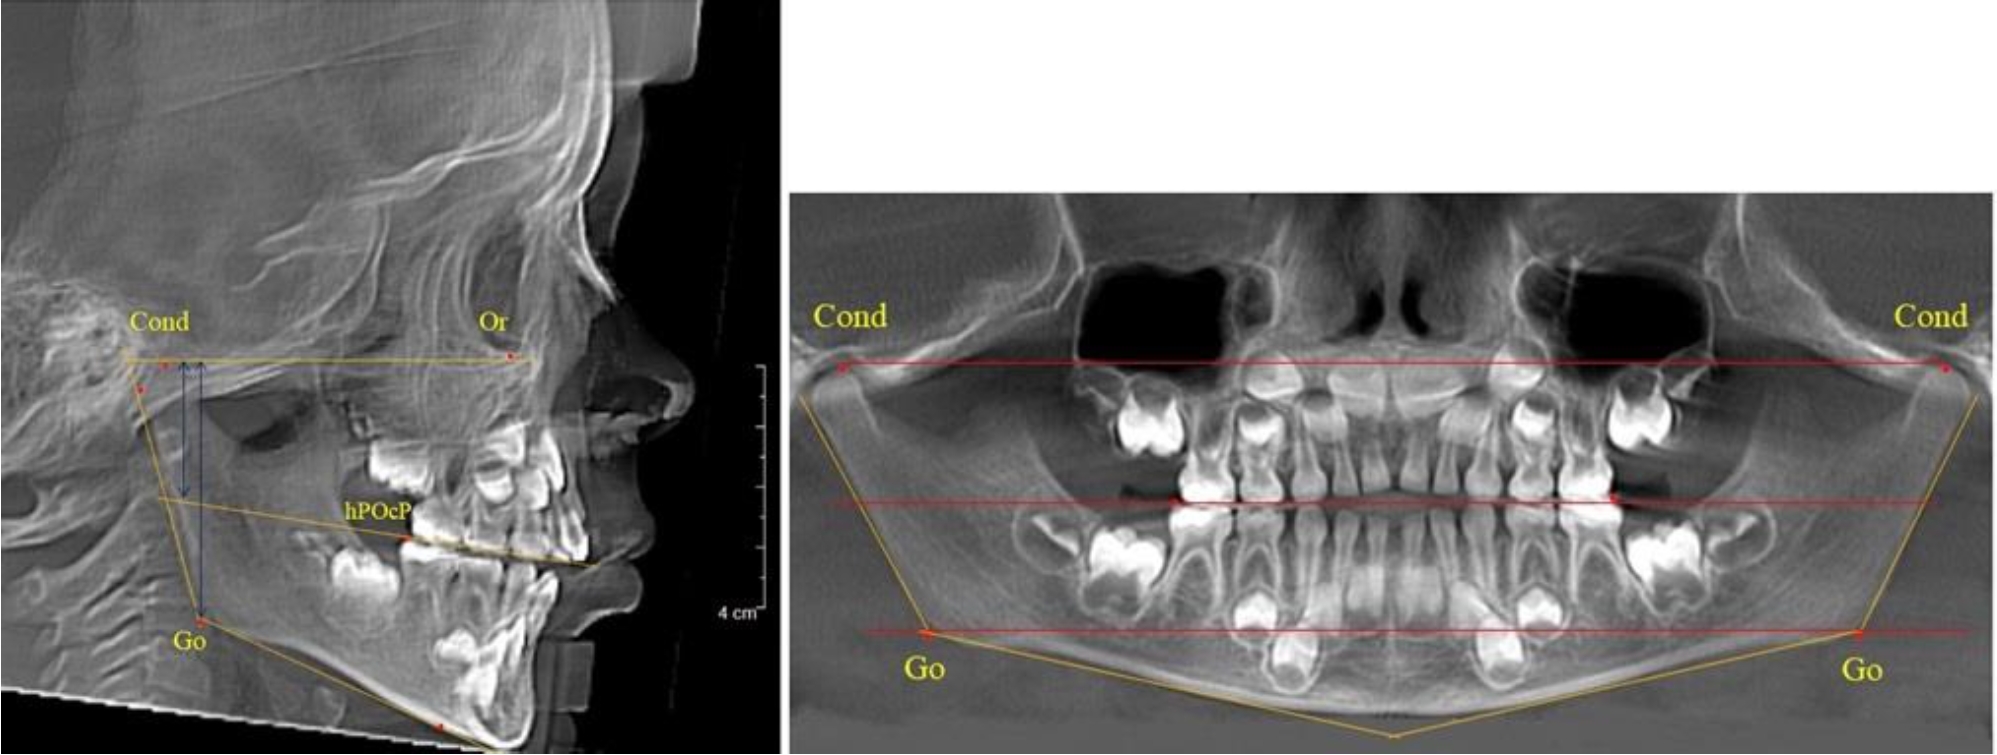

В 4-й группе были проанализированы 12 комплектов рентгенограмм, что составило (11,32 ± 3,08) % от общего числа. На всех рентгенограммах произошла полная смена всех молочных зубов постоянными. Окклюзионная линия делила ветвь на два отдела (рис. 4).

Рис. 4. ТРГ пациента после смены всех молочных резцов

Высота ветви у детей 4-й группы составляла (54,27 ± 2,59) мм, что было достоверно больше, чем у детей 1-й группы (р ˂ 0,05). При этом высота верхней окклюзионно-суставной части была (32,51 ± 1,72) мм, а нижней – (21,76 ± 1,42) мм. Высота верхней части была больше нижней, что и определяло особенности соразмерности частей ветви нижней челюсти в анализируемый возрастной период.

Относительные показатели соразмерности частей ветви нижней челюсти показали, что отношение высоты верхней части ветви к нижней в среднем составляло 1,49 ± 0,12. Отношение общей высоты ветви к верхней ее части составляло 1,67 ± 0,14, а отношение общей высоты ветви к нижней ее части было 2,49 ± 0,15, что и определяло особенности соразмерности частей ветви нижней челюсти в анализируемый возрастной период.

В 5-й группе были проанализированы 14 комплектов рентгенограмм, что составило (13,21 ± 3,29) % от общего числа. На всех рентгенограммах отмечен очередной этап подъема высоты прикуса, обусловленный прорезыванием вторых постоянных моляров. Окклюзионная линия делила ветвь на два отдела (рис. 5).

Рис. 5. ТРГ и ОПТГ пациента после смены молочных зубов и прорезывания вторых постоянных моляров